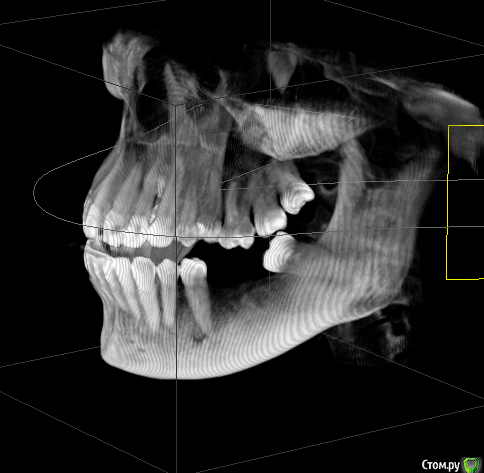

Mariia Опубликовано 9 ноября, 2017 Поделиться Опубликовано 9 ноября, 2017 Уважаемые доктора, добрый день!Посоветуйте, пожалуйста, что можно сделать в моем случае. Давно нет 3-х зубов (более 10 лет), стали стираться 7-ки справа, верхняя 6-ка слева стала опускаться.После нескольких консультаций окончательно запуталась в планах лечения.Понятно, что необходимо устанавливать 3 импланта, но как это сделать? - предлагают ортодонтическое лечение на верхней 6 справа (ставить миниипланты и поднимать) и верхней 7 слева (сдвигать ее, освобождая место для установки импланта, полностью имитирующий нормальный жевательный зуб). - и второе мнение: 7 не сдвигать, поставить вкладку, а 6 спиливать, депульпировать (скорее всего) и ставить керамическую вкладку. 6-ку не поднимать, так как гайморова пазуха находится близко к корню. Собственно, в комплексе с ортодонтией все лечение выходит очень дорогим.Что скажете? КТ по ссылкеhttps://yadi.sk/d/cSYIaF3p3PZFnb Ссылка на комментарий

Bier Опубликовано 10 ноября, 2017 Поделиться Опубликовано 10 ноября, 2017 Посмотрел Вашу КТ.Справа в принципе можно ортодонтией не заниматься, а поставить имплантат в позицию 16зуба, коронка будет чуть меньше стандартной. Проблемы скорее всего не будет. Слева ситуация сложнее. Надо удалить 28,38 зубы, внедрить на миниимплантатах 26з и имплантировать 36,37з Ссылка на комментарий

колесников Опубликовано 10 ноября, 2017 Поделиться Опубликовано 10 ноября, 2017 48,28,38 удалить. Импланты 16,36,37. Пластика десны в области имплантов 36,37. Керамическая вкладка (пломба) на 17,26,27 Ссылка на комментарий

Mariia Опубликовано 12 ноября, 2017 Автор Поделиться Опубликовано 12 ноября, 2017 Добрый день, и еще одно мнение: 7 справа не трогать, поставить вкладку. А в будущем провести ортодонтическое лечение: 7ку или поставить на место 6ки или отодвинуть и освободить место под полноценный имплант (доктор видит риск резорбции и травмы соседних зубов из-за недостатка места, тонкий имплант ставить не рекомендует)А слева предлагает сделать подсадку костной ткани на нижней челюсти - 6 и 7 зубы, чтобы поставить полноценный имплант (тонкий не рекомендует, хотя на прошлых консультациях мне предлагали как раз полноценный и костной ткани хватало). К сожалению, по моей КТ не показали, где идет истончение. Предложил сделать на другом оборудовании и с другим просмотрщиком, чтобы аргументировать свою точку зрения. Соответственно, 8 удаляем. Настолько ли моя КТ не информативна? Нужна ли КТ на операции? Возможен ли такой план лечения? Есть ли какой-то стандартизированный план лечения по моему случаю? Фото выложу чуть позже.Спасибо. Ссылка на комментарий